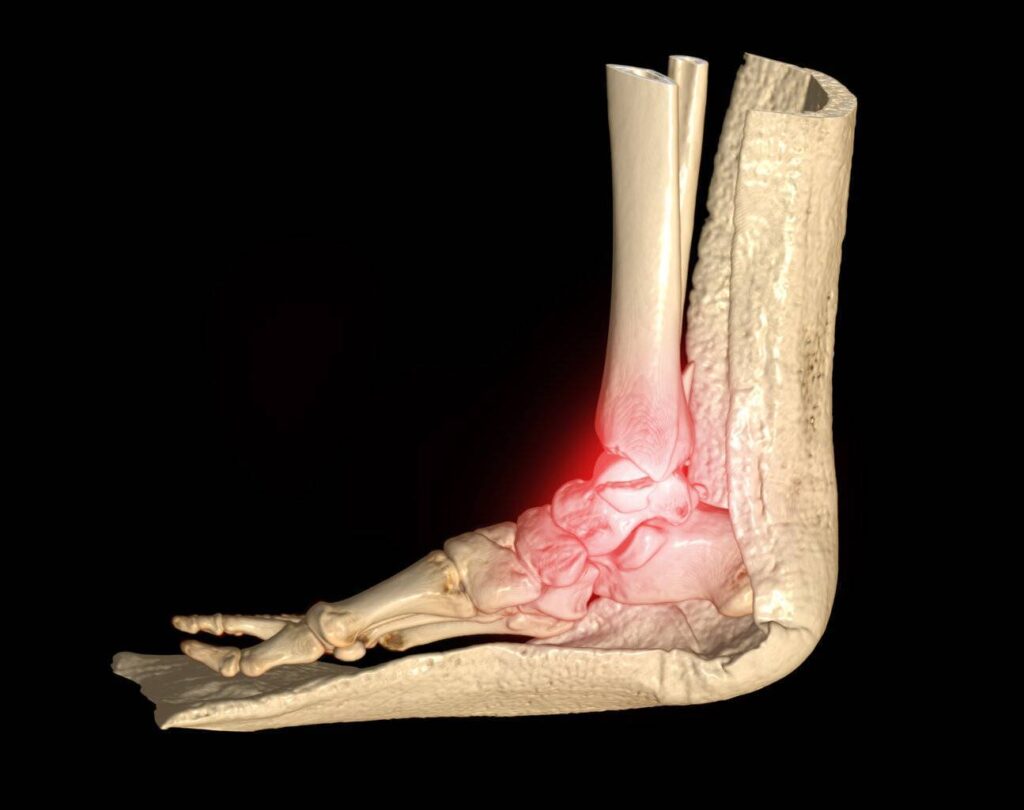

Ein CT Sprunggelenk-Scan ist ein medizinisches bildgebendes Verfahren, das Röntgenstrahlen und Computertechnologie verwendet, um Schnittbilder des Knöchelgelenks zu erstellen. Diese Bilder liefern detaillierte Informationen über die Knochen, Gelenke, Bänder, Sehnen und Weichteile im Knöchel. CT-Scans sind besonders nützlich zur Diagnose und Bewertung einer breiten Palette von Knöchelerkrankungen, einschließlich Frakturen, Verstauchungen, Arthritis und anderen muskuloskelettalen Problemen.

- Präzise Diagnose: CT Sprunggelenk-Scans bieten hohe Bildauflösung und 3D-Darstellungen, die detaillierte Einblicke in die Anatomie des Sprunggelenks ermöglichen. Dies führt zu einer präzisen Diagnose von Verletzungen und Erkrankungen.

- Vielseitige Anwendung: Neben der Frakturdiagnose sind CT-Scans nützlich für die Beurteilung von Weichteilgewebe, die Erkennung von Tumoren, präoperative Planung und die Verlaufskontrolle von Erkrankungen im Sprunggelenk.